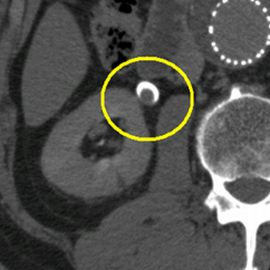

[腎盂がん(右)] 手術:右腎尿管全摘術

CT画像